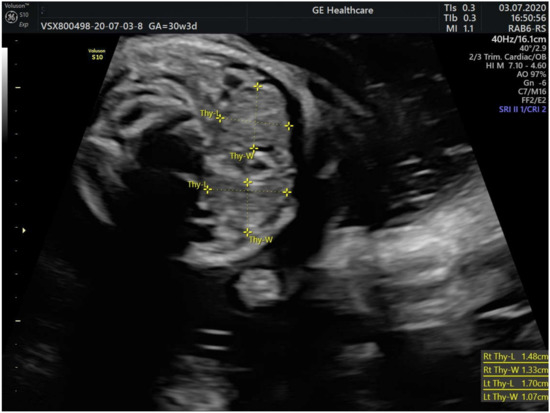

2. Case Presentation